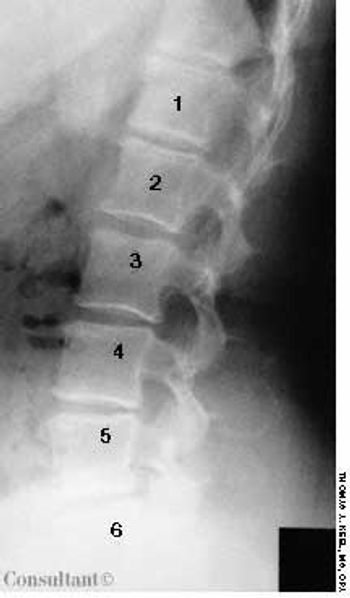

After 6 weeks of persistent low back pain, an overweight 72-year-old woman sought medical evaluation. There was no history of trauma.